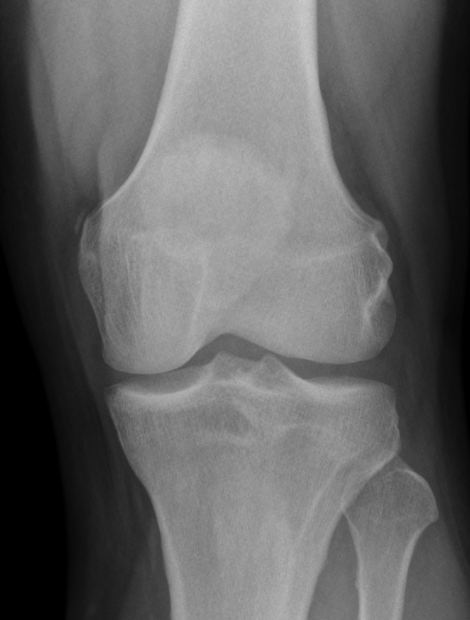

3. Pellegrini Stieda Lesion